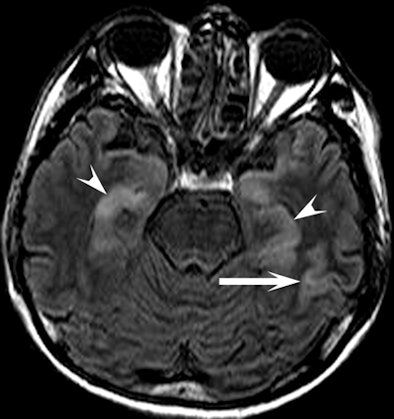

| Clinical images of a 51-year-old man found unconscious with a Glasgow Coma Scale score of 7 and withdrawal to pain. Above image shows fluid-attenuated inversion recovery, while below is a diffusion-weighted image that shows an increase in signal intensity in the head, body, and tail of the hippocampus bilaterally (arrowheads) and in the cerebral cortex (arrow). All images courtesy of Radiology and the National Neuroscience Institute. |